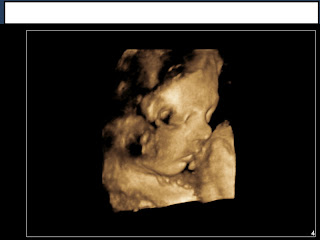

And now, with what's unfolded over the last few days, I'm really glad that we have a name for you. Last week, we found out that there is a mass in your chest and the doctors aren't sure what it is. Absolutely everything else about you--every single thing--looks perfectly normal, right down to your swallowing and your frequent practice breathing. We are praying for you, Lainie Rae, and so are lots of other people: That this is nothing serious, just a harmless little anomaly that doesn't impact you negatively at all, or that Jesus takes it away entirely before you're born. Tomorrow we get to take another peek at you and hopefully figure out what exactly this mass is.

So you just keep growing away in there, take lots of naps, and maybe tomorrow morning you can turn belly-side-up so we can see your chest a little better.

Nikki, she is a BEAUTY! And she has your nose!!! So precious!